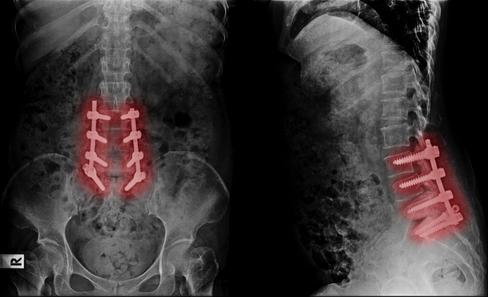

Back Pain should not mean fusion, screws, and lengthy recoveries Regenerative Medicine is changing how back pain is solved.